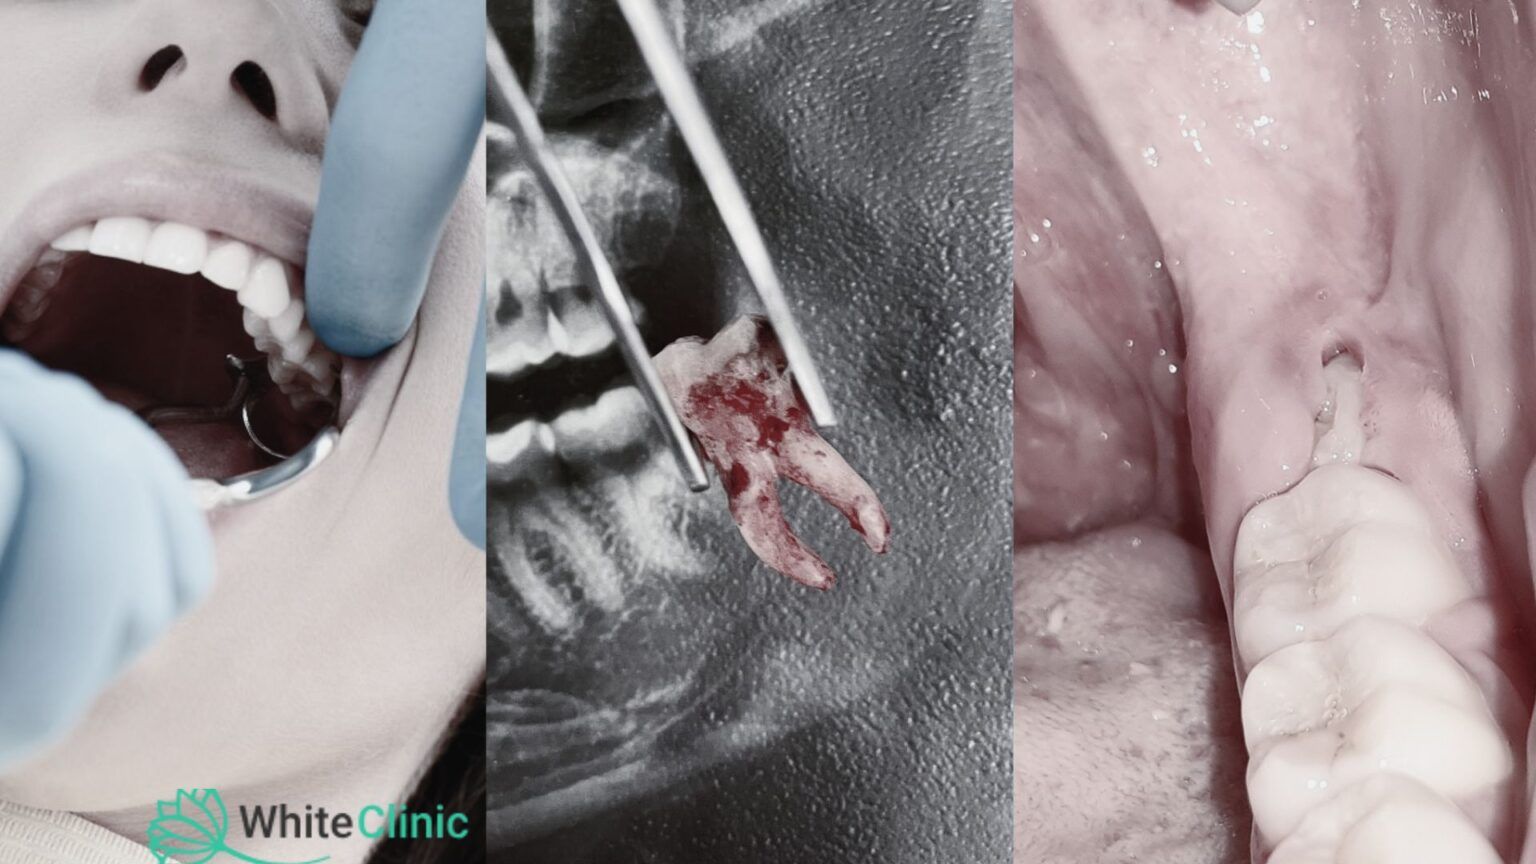

У стоматологічній практиці існують різні типи операцій по видаленню зубів, які застосовуються в залежності від конкретної ситуації пацієнта.

Просте видалення зуба виконується, коли зуб видно в ротовій порожнині і його можна легко витягнути за допомогою стандартних стоматологічних інструментів. Цей тип видалення зазвичай проводиться під місцевою анестезією, щоб забезпечити безболісне лікування. Наприклад, якщо у вас є сильно пошкоджений карієсом 6 зуб, який неможливо врятувати, стоматолог може провести просте видалення.

Хірургічне видалення зуба необхідне в більш складних випадках, коли зуб не можна видалити за допомогою стандартних інструментів. Це може бути випадок, коли зуб ще не повністю прорізався, зламався на рівні ясен або розташований під неправильним кутом. Операція видалення зуба часто включає розріз ясен для доступу до зуба і може вимагати розділення зуба на частини для полегшення його видалення. Хірургічне видалення також застосовується для зубів мудрості, які часто прорізуються неправильно або залишаються під яснами. Коли зуб сильно пошкоджений або зламався, можуть залишитися корені, які потребують видалення. Видалення залишків коренів проводиться хірургічним шляхом, щоб запобігти інфекціям і іншим ускладненням. Цей тип видалення також може бути частиною підготовки до імплантації зубів.

Процес починається з консультації та діагностики. Стоматолог проводить огляд ротової порожнини, робить знімок щелепи, щоб оцінити стан зуба та навколишніх тканин. Це допомагає визначити, чи потрібно видаляти зуб, і який метод видалення буде найбільш відповідним.

Процедура видалення зуба у White Clinic залежить від складності випадку і може бути проведена різними методами. Спочатку стоматолог вводить анестезію, щоб знеболити ділянку навколо зуба. Для простого видалення зуба використовуються спеціальні інструменти, щоб розхитати зуб, після чого він обережно витягується з лунки.

У випадках складного видалення, коли зуб зламаний або розташований під яснами, може знадобитися хірургічне втручання. Стоматолог робить невеликий розріз на яснах для доступу до зуба. У деяких випадках зуб може бути розділений на кілька частин для полегшення його видалення. Після видалення зуба стоматолог може накласти шви для прискорення загоєння.

Операція видалення зуба мудрості часто вимагає особливої уваги через неправильне розташування або часткове прорізування зубів мудрості. Стоматолог робить розріз на яснах і, за необхідності, видаляє кісткову тканину, щоб отримати доступ до зуба. Зуб може бути розділений на частини для полегшення його видалення, а після видалення зуба накладаються шви.